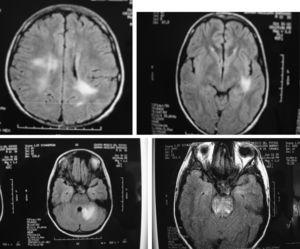

In our group of six SLE patients with severe central nervous system (Table 2) disease we observed an excellent response to Rituximab therapy. In all cases no permanent damage or disability was observed, including in the two patients with transverse myelitis, one with meningo-encephalitis, one with cerebellar syndrome, one with hemorrhagic stroke and one with severe choreoathetotic movements. Patients with transverse myelitis received rituximab in their second (case 1) and third (case 2) episodes, and in this last episode of the second patient who had sensitive level and distal dysesthesias, we decided do not use methylprednisolone pulses (mPDN), and in both patients, in their relapses, we did not use cyclophosphamide; both of them, had complete resolution of this severe neurologic involvement. We realized MRI studies only in their 1st myelitis presentation, and in both cases, were normal. Patient 4, had MRI totally normal, in fact she was well until 3 months after her had received rituximab 1 g, when she presented again a cerebellar affectation with ataxia and a new MRI study was also normal; she was treated with rituximab 1 g and mPDN pulses with complete resolution 15 days after and she continue healthy. The other 3 patients have had MRI abnormalities; in Fig. 1, we show some of images of MR related to patient 3, who achieve complete clinical remission and IRM normal, study that was taken 2 months after were treated with rituximab 1g; he is healthy 3 years after and is being treated with hidroxi-chloroquine and simvastatine.

Fig. 1. RMI with various hyperintensive lesions which disappear after therapy with rituximab (Patient described above as case 4).

- 4. A 15 years old male with SLE and a history of encephalitis and meningitis that was treated with prednisone and complete antituberculous therapy (9 months). He had been well, but he was admitted because severe headache with an MRI showing new brain lesions (Fig. 1), and manifestations of renal damage with a diminished creatinine clearance (70 ml/min). Methylprednisolone pulses (1 g/day for 3 days), besides 2 g of Rituximab divided in two doses was prescribed. One month later most clinical manifestations improved, and five months later, the lesions seen in the MRI disappeared. At this time, a renal biopsy showed mild endothelial thickness without glomerulonephritis, with scarce granular deposits of IgG, IgM, IgA and C3. Three years after Rituximab therapy the patient remains asymptomatic, with creatinine clearance of 123 ml/min, a normal urine test, with no glucocorticoids and receiving only low doses of atorvastatine and hydroxychloroquine.